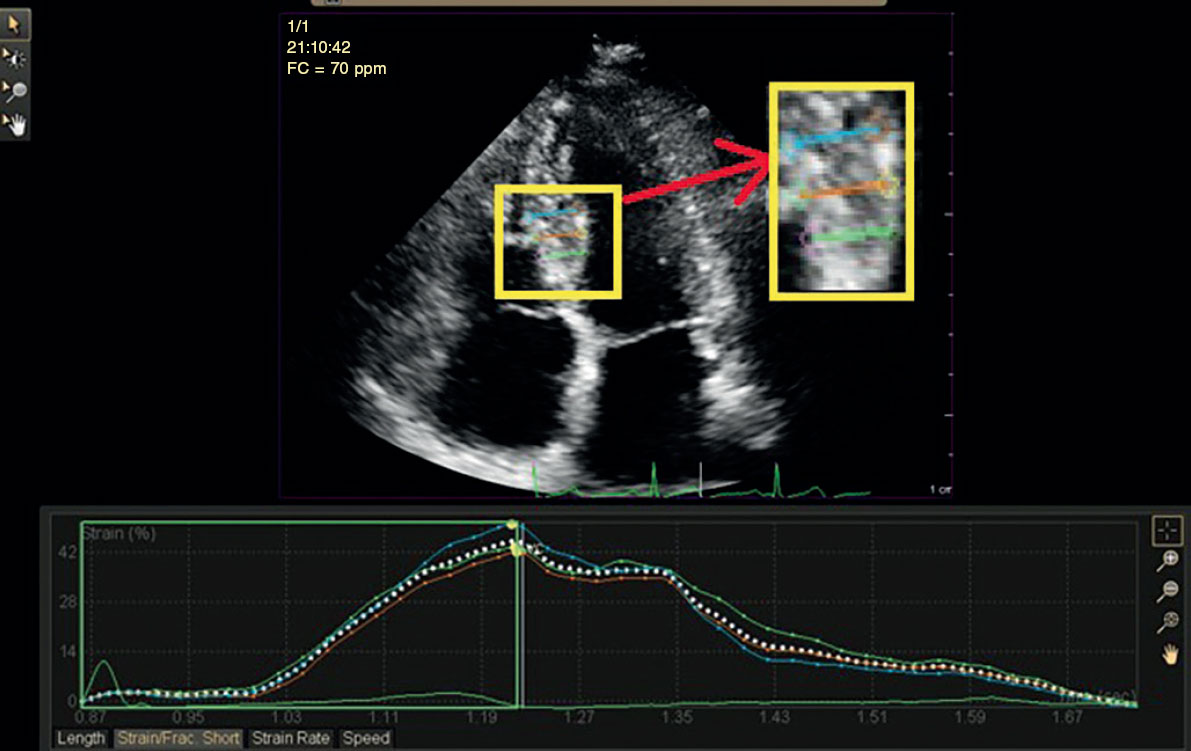

Figura 2. Análisis de deformación radial regional de un participante del estudio con cardiopatía isquémica estable que muestra un 42% de deformación en el segmento inferoseptal medio.